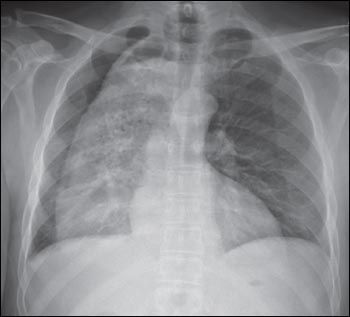

Results of laboratory studies were normal. A chest radiograph showed a markedly dilated esophagus and a possible small pleural effusion on the right side; no necrotic debris or undigested food material was noted. The cardiac silhouette showed normal borders. The trachea was midline.